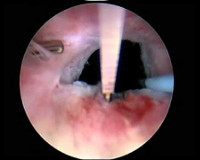

N32.0 Обтурация шейки мочевого пузыря